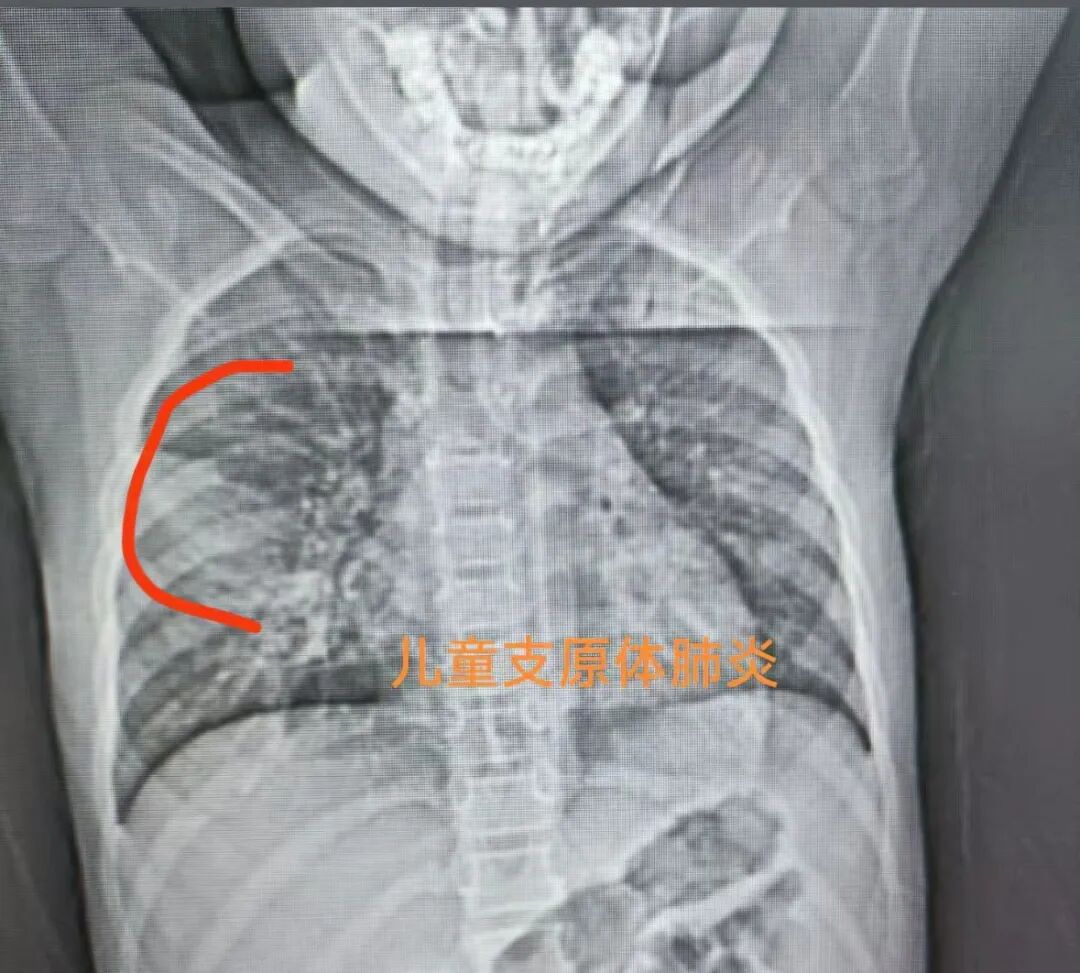

其次支原体肺炎呢分为轻症和重症

所以咱们来看重症的标准

第一,持续高热超过五天不见好

每天都有39度以上的高烧

或者说是每天都有发烧,超过七天不见好

第二,出现喘息、呼吸急促、呼吸困难、胸痛、卡血等等

第三,安静状态下,血氧饱和度小于等于93

出现了这些就一定要住院

重症支原体肺炎推荐阿奇霉素输液治疗

连用七天左右,间隔3到4天之后

可以开始第二个疗程,总疗程依据病情而定

多为2到3个疗程